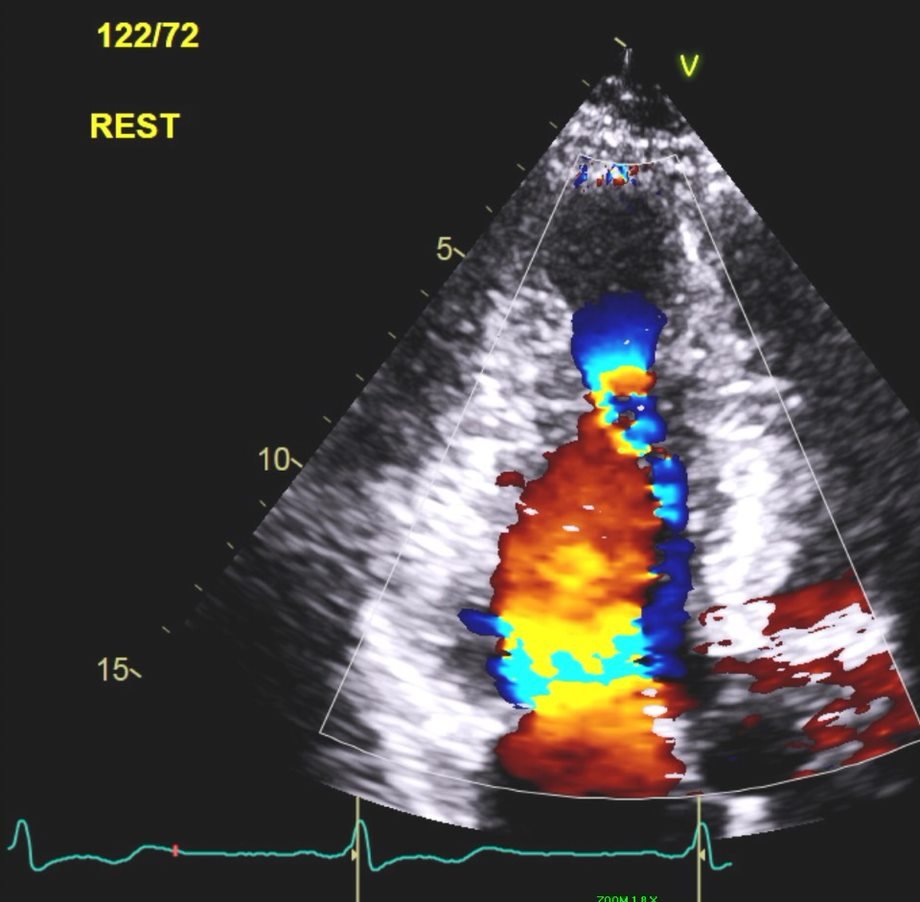

3/5 This characteristic flow pattern is also visualized on 2D color flow (still images below).

4/5 Left: Flow during IVRT (blue jet/arrow).

Right: Flow after MV opening (red jet). Note the two flows "colliding" in the mid ventricle.